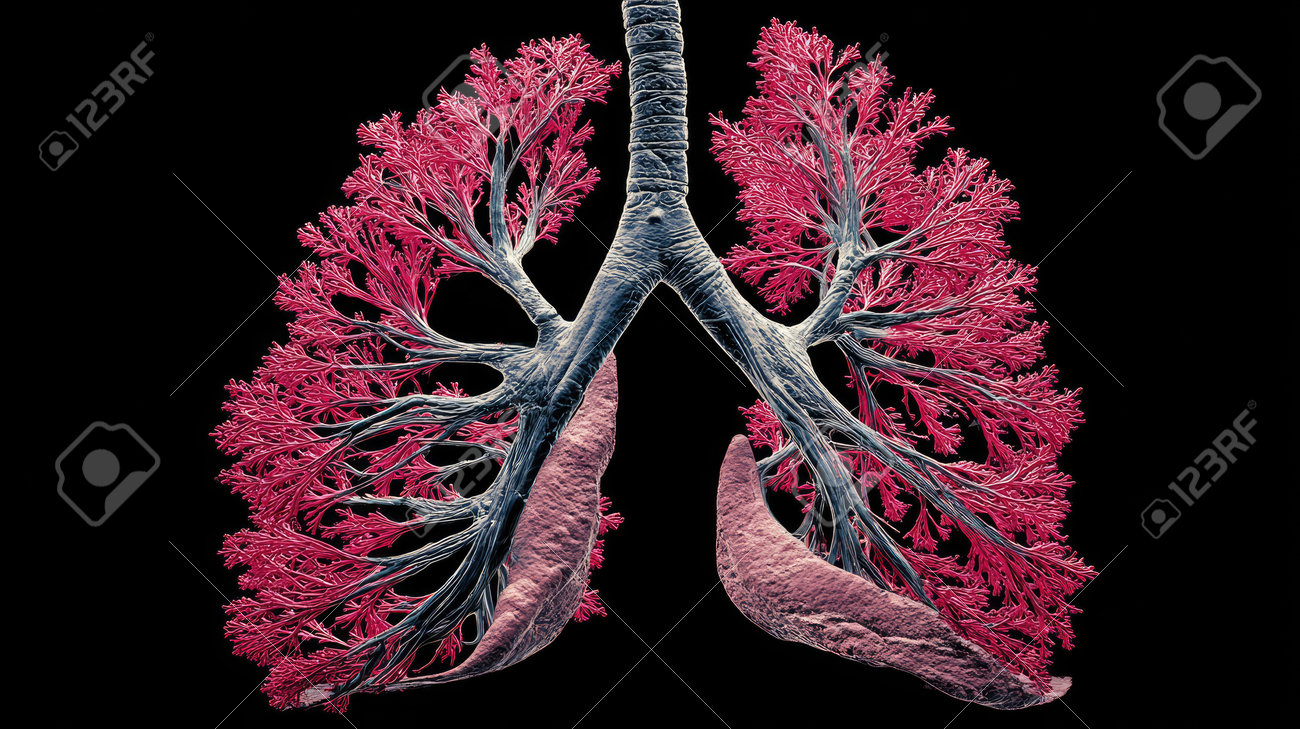

abdominal, analysis, anatomy, biology, black and white, body, bone, clinical, closeup, condition, data, department, detail, education, framework, health care, healthcare and medicine, healthy lifestyle, horizontal, hospital, human, imaging, internal, kidney, lifestyles, lung, medicine, monochrome, muscle, no people, organ, physician, presentation, procedure, professional, research, rib, scan, scientific, section, skeleton, spine, structure, study, system, tissue,